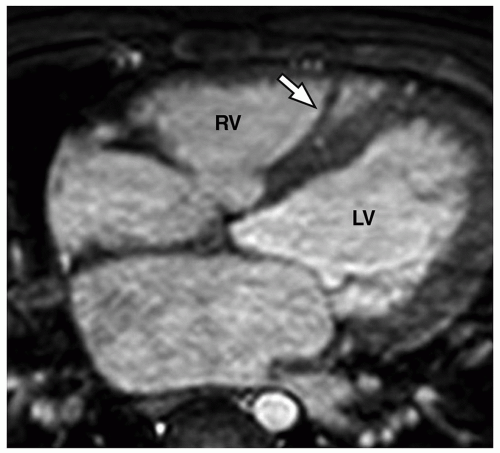

moderator band in which compartment?

RV

moderator band connects which structures?

IV septum anterior papillary muscle